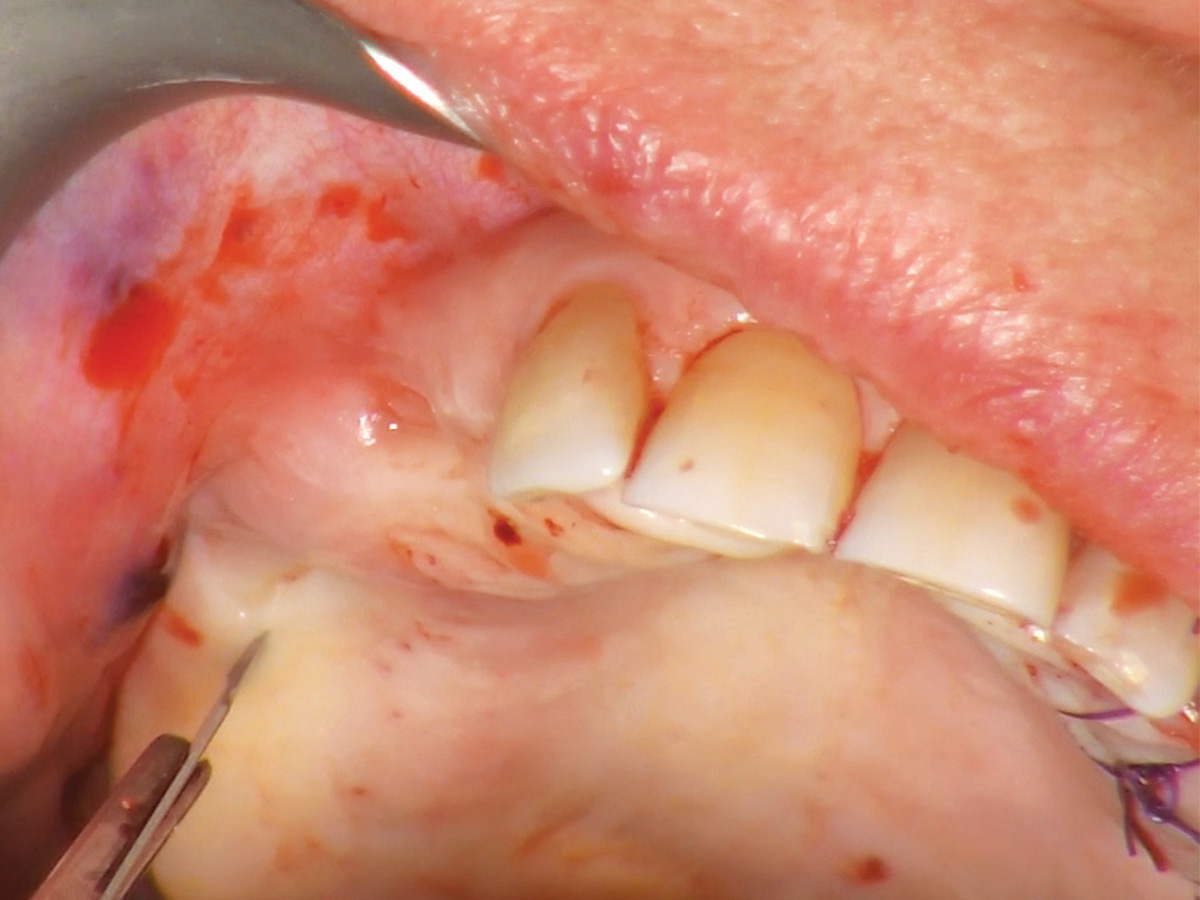

Abbildung 7

Einsetzen der Gingivaformer nach vier Monaten.